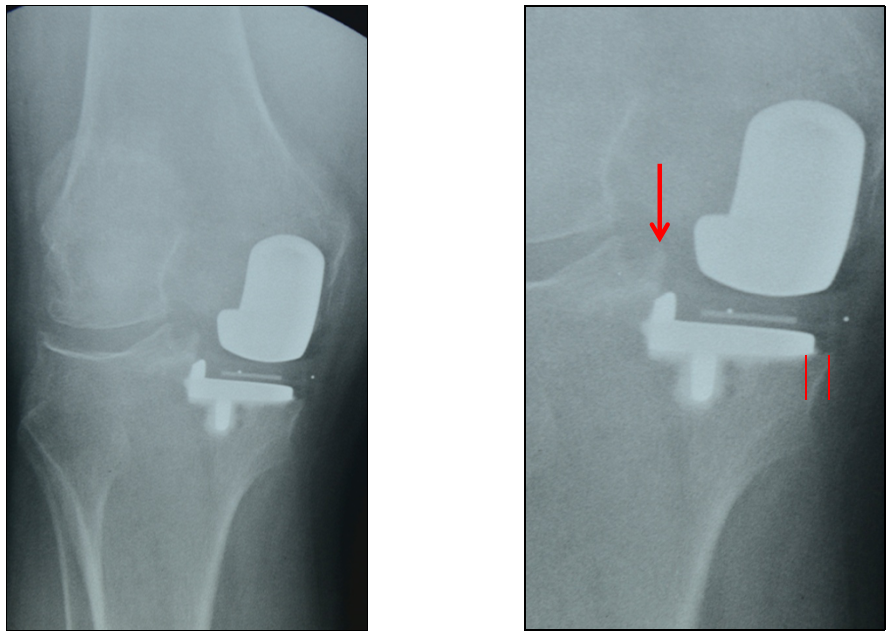

胫骨假体中立位(横断面:无内外旋)

胫骨假体内旋

胫骨假体外旋